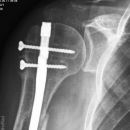

Subcapitale Fraktur und Tuberculum majus